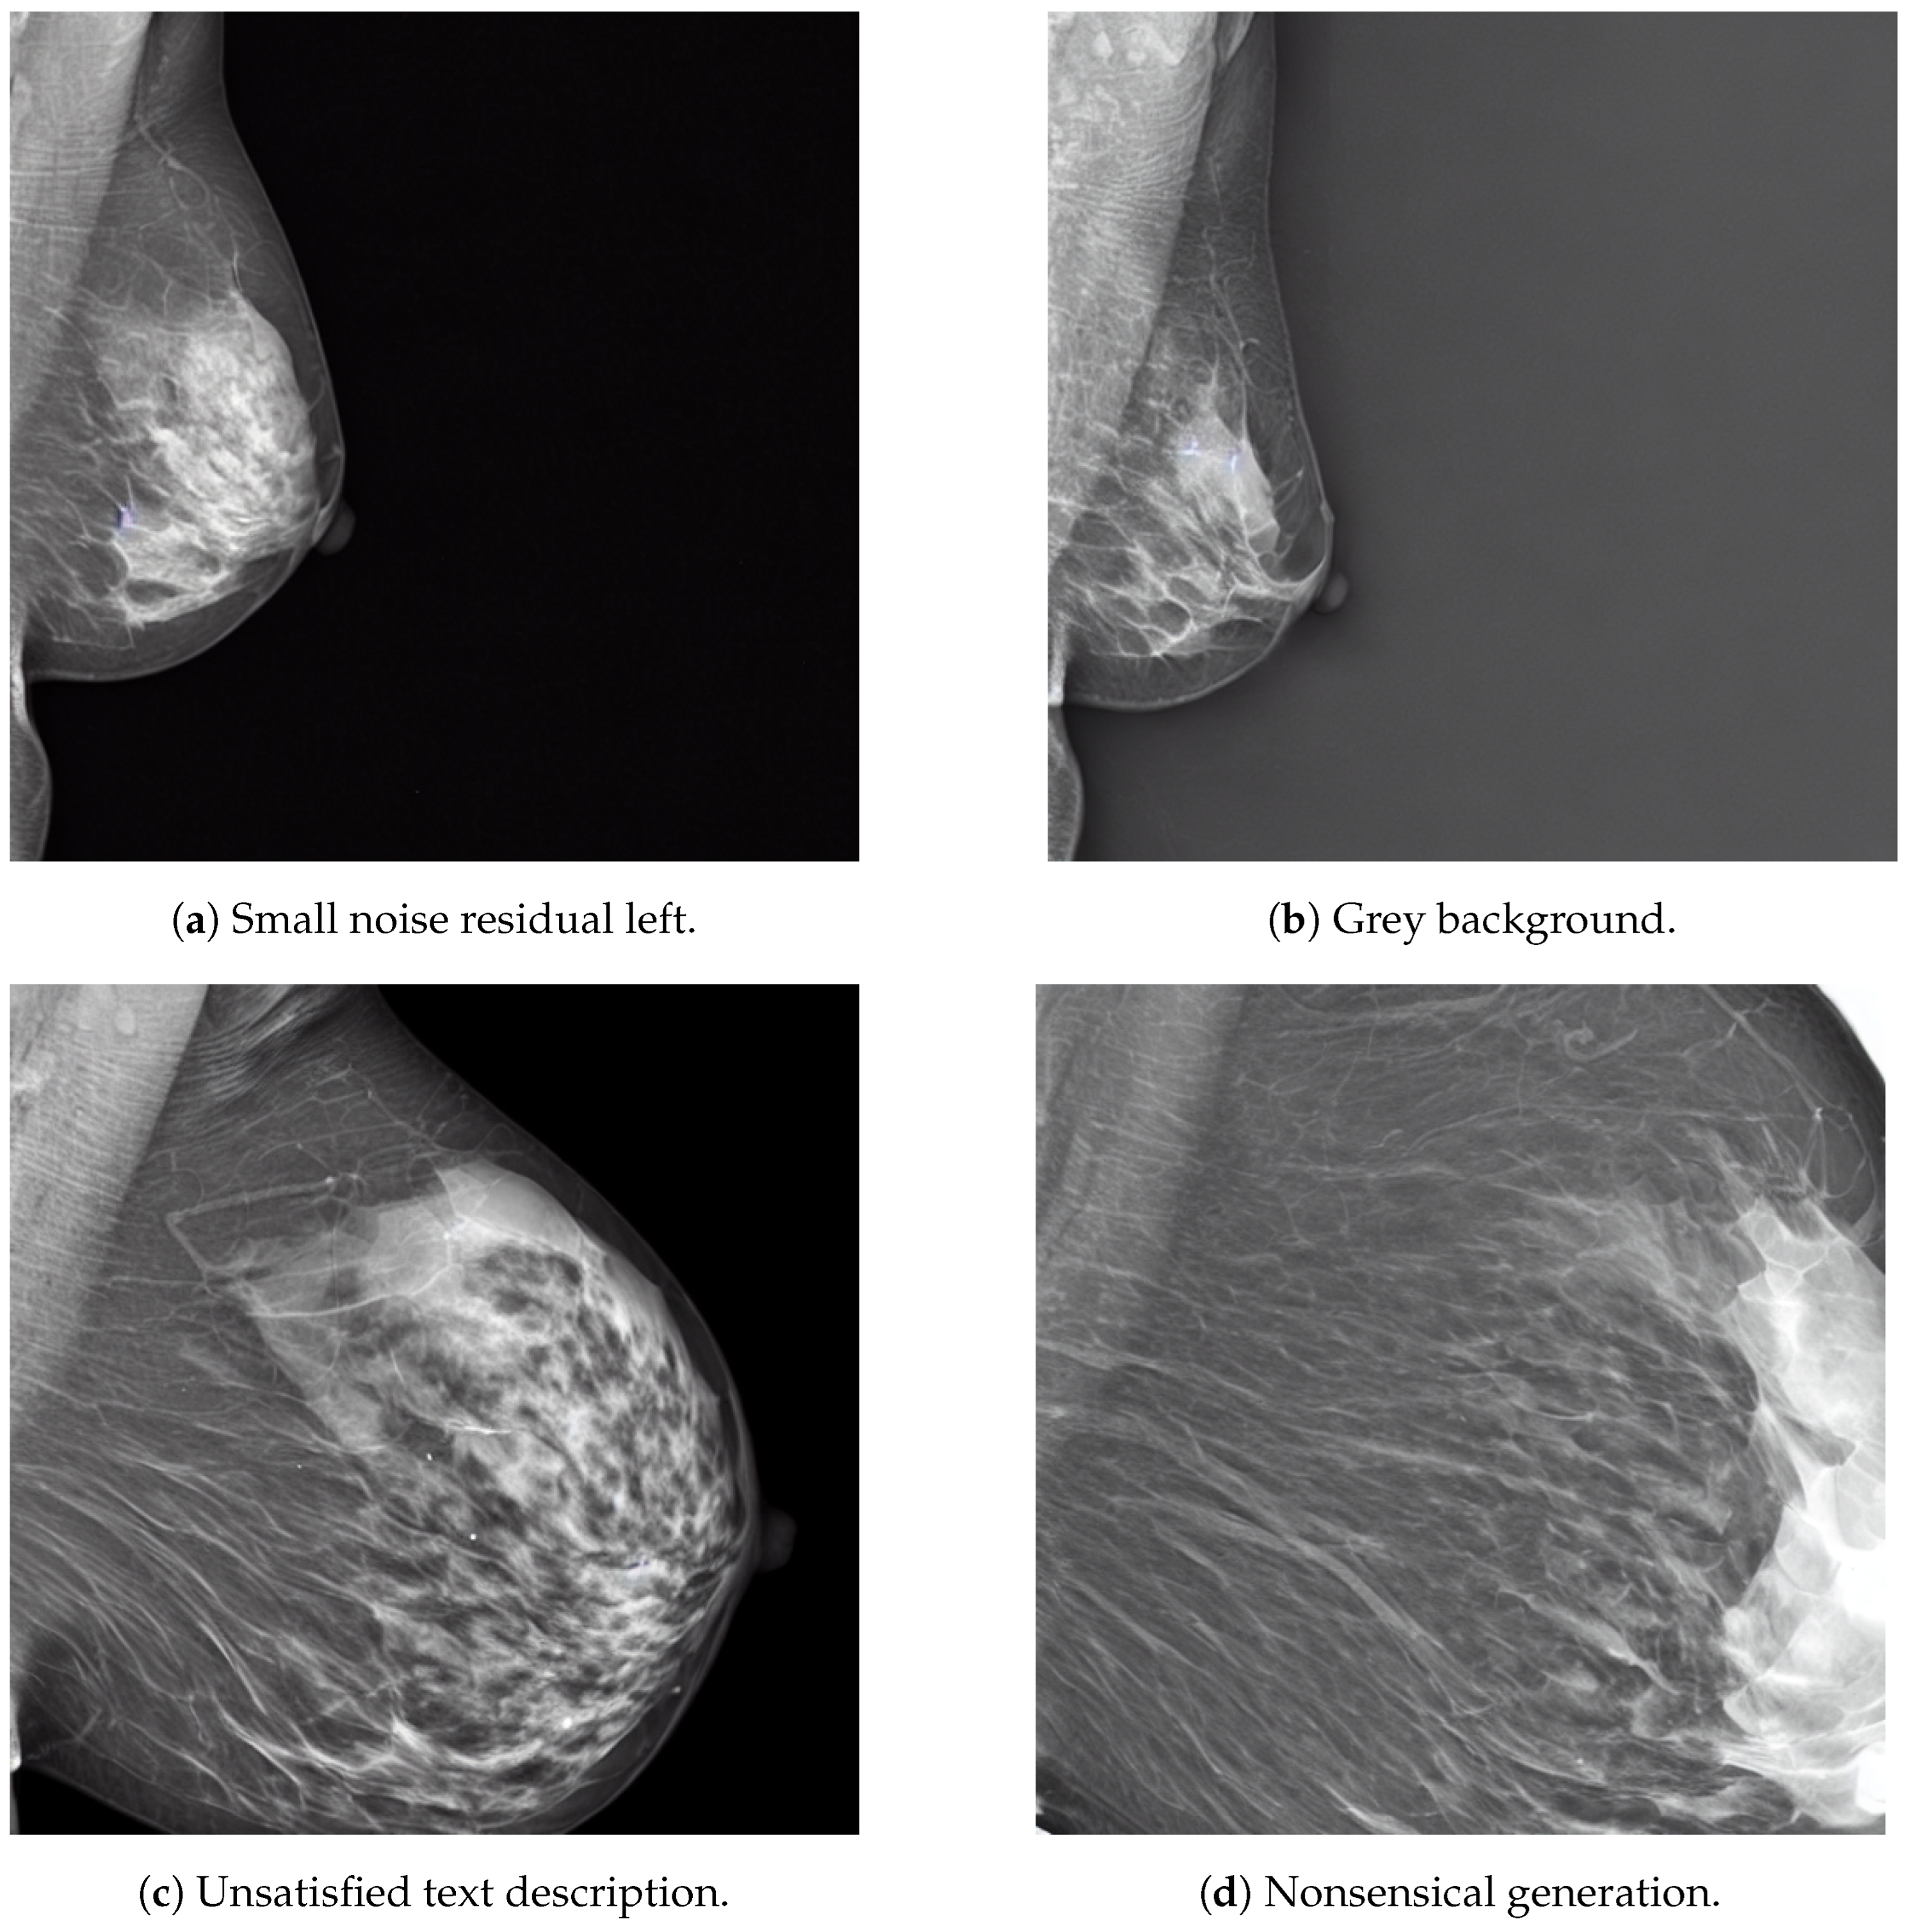

Nevertheless, selecting the proper diffusion hyperparameters is challenging as, in some cases, the model may generate images with errors. Figure 20 shows some of the common generation issues faced by our SD models, in this case coming from the same text prompt at a guidance scale of 4.

Figure 20.

Examples of unsuccessful image generation of the combined dataset models coming from the same text prompt. The prompt was “A siemens mammogram in MLO view with small area and very high density” with a guidance scale of 4.

These generation errors have different possible solutions, each of them with their drawbacks and limitations. For instance, the noise residuals in Figure 20a could be removed if the inference diffusion steps are increased, leading to longer generation time. The gray background issue in Figure 20b could be solved by using a negative prompt, which essentially specifies some features in the image that must be avoided, such as “white background” or “no black background”. The unsatisfied prompt description of Figure 20c and the nonsensical generation of Figure 20d could be solved by increasing the guidance scale at the expenses of the generation diversity, as previously discussed. Therefore, the selection of the optimal diffusion hyperparameter must be defined for each individual model empirically. For instance, as Table 3 shows, the optimal guidance scale value may not be the same across models. Moreover, in some cases, such as in the Siemens model, the effect of the guidance scale on the MS-SSIM value may not be significant and other metrics for image diversity must be computed for a better informed decision.